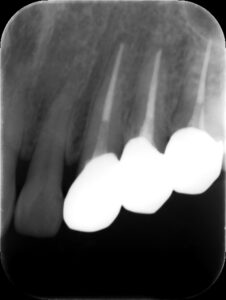

初診時レントゲン。他院で1年以上かけて根管治療を行っているが痛みや歯茎の腫れが引かずに来院。元々は歯髄が生きていた生活歯の抜髄を行ったケース(イニシャルトリート)。同時に3本もの歯を抜髄して長期に根管治療を行う診断に問題があると言わざるを得ない。患者さんは心身ともに疲弊し、歯科治療への不信が高まってしまうのも無理はない。まずは、現状の説明と解決策を提示し、歯科治療への不安を取り除くところから治療が始める。